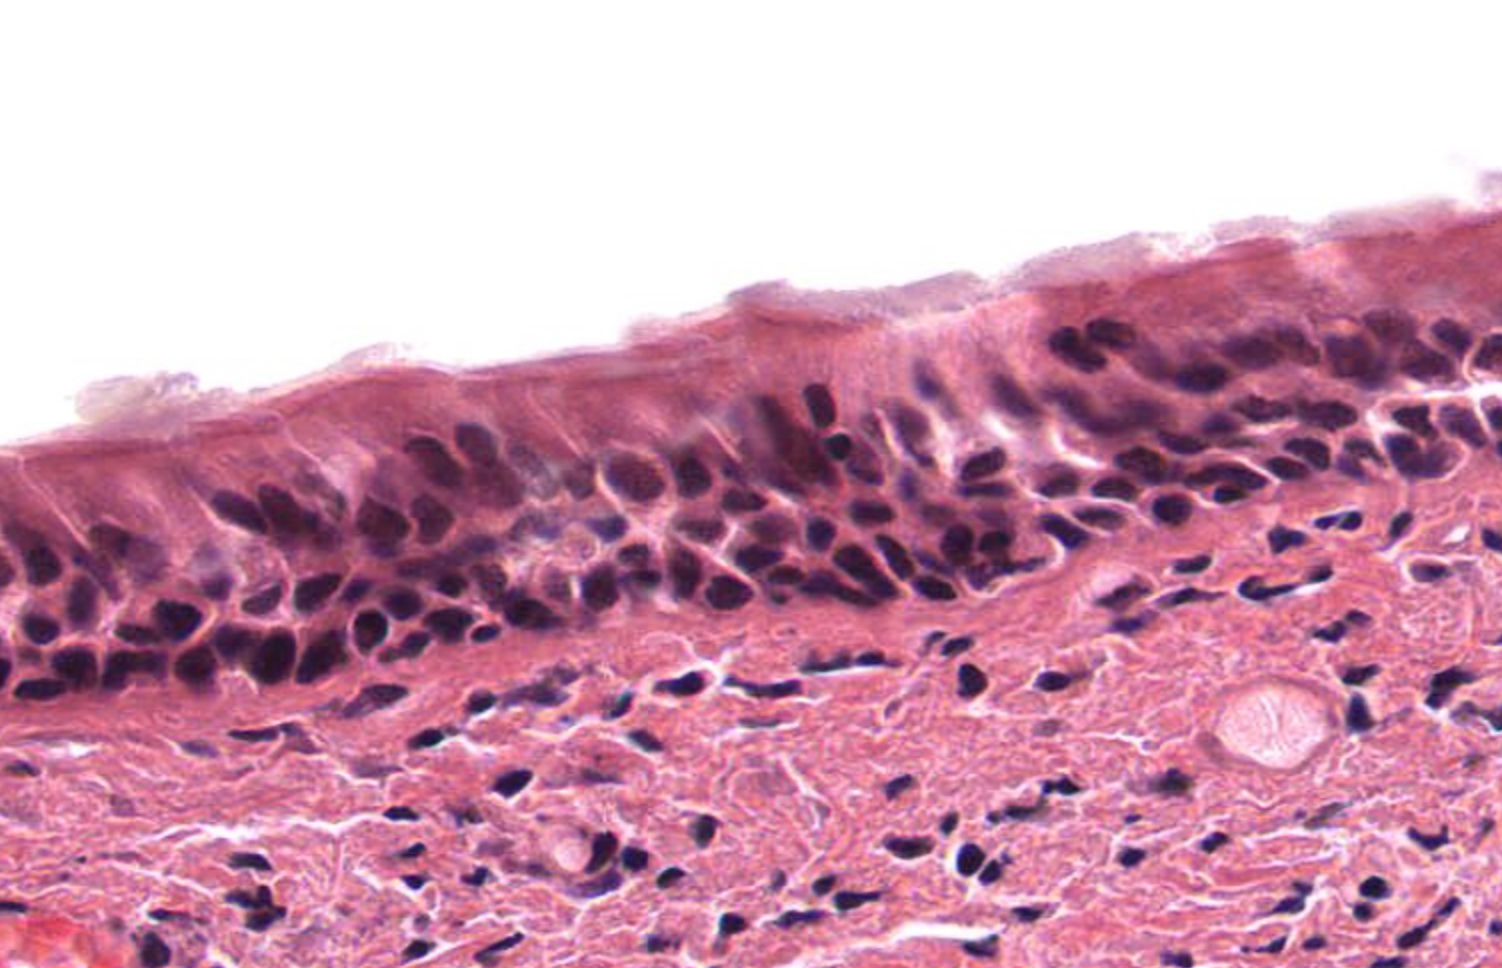

term image

Tissue: simple squamous epithelium

Location:

• kidneys

• alveoli

• lining of heart, blood and lymphatic vessels

• ventral body cavity lining

Function:

• diffusion and filtration

• secretes lubricating substance